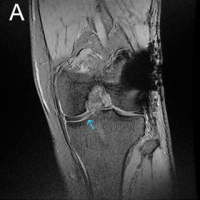

In addition, a Morel-Lavallée lesion was noted near the right kidney and was subsequently debrided with a drain in place. Initial ultrasound imaging of the abdomen revealed minimal free fluid, and the patient was stabilized with hemoglobin levels raised to 10 g/dL. Surgical intervention began with stabilization of the spine through open reduction and internal lumbo-pelvic fixation. The patient was then repositioned to fix the right acetabular fracture using a modified Stoppa approach (Fig. 2).

Figure 2: Post-operative X-ray of lumbopelvic fixation (L5-Iliac); L1 vertebroplasty; Right acetabulum anterior column open reduction internal fixation with 14-hole Recon plate.